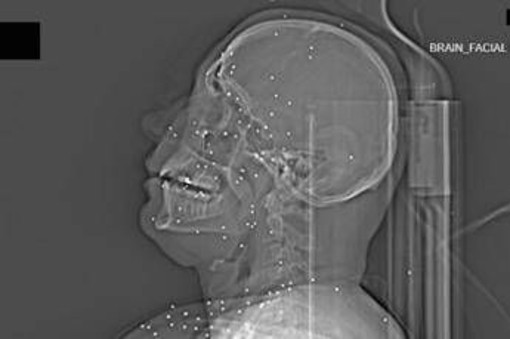

Il volto di Anahita – nome di fantasia, poco più che ventenne – appare come un cielo notturno attraversato da punti luminosi. Piccole sfere metalliche, da 2 a 5 millimetri, disseminate sul viso, nelle orbite oculari, persino nella massa scura del cervello. Sono proiettili “birdshot”, pallini da caccia sparati da un fucile a pompa. A distanza ravvicinata, spiegano gli esperti, non sono affatto “meno letali”: possono frantumare ossa, devastare tessuti molli, perforare facilmente un bulbo oculare. Anahita ha perso almeno un occhio, forse entrambi.

Quell’immagine non è un caso isolato. Fa parte di oltre 75 set di esami diagnostici provenienti da un singolo ospedale di una grande città iraniana, raccolti nel corso di una sola serata, durante la stretta repressiva di gennaio. Una concentrazione temporale che, già di per sé, racconta una dinamica da “mass casualty”, evento con numerose vittime simultanee, tipico degli scenari di guerra o dei grandi disastri.

Le valutazioni, condotte congiuntamente dal Guardian e dalla piattaforma di fact-checking Factnameh, sono state affidate a un panel indipendente di specialisti internazionali: medici d’urgenza, radiologi, esperti di trauma imaging e balistica. Un ex medico iraniano di pronto soccorso, anch’egli consultato, ha confermato la coerenza del software utilizzato per gli esami e l’assenza di segni di manomissione. Gli esperti precisano che, senza cartelle cliniche complete, non è possibile formulare diagnosi definitive sui singoli pazienti. Ma il quadro complessivo, spiegano, è inequivocabile.

Accanto ai colpi di grosso calibro, emerge con forza un altro elemento: l’uso sistematico dei pallini metallici. L’Iran è tra i pochi Paesi in cui le forze di sicurezza impiegano birdshot metallico. A lunga distanza, i pallini si disperdono e colpiscono indiscriminatamente. A distanza ravvicinata, diventano devastanti: decine, talvolta centinaia di micro-proiettili che penetrano simultaneamente nei tessuti.